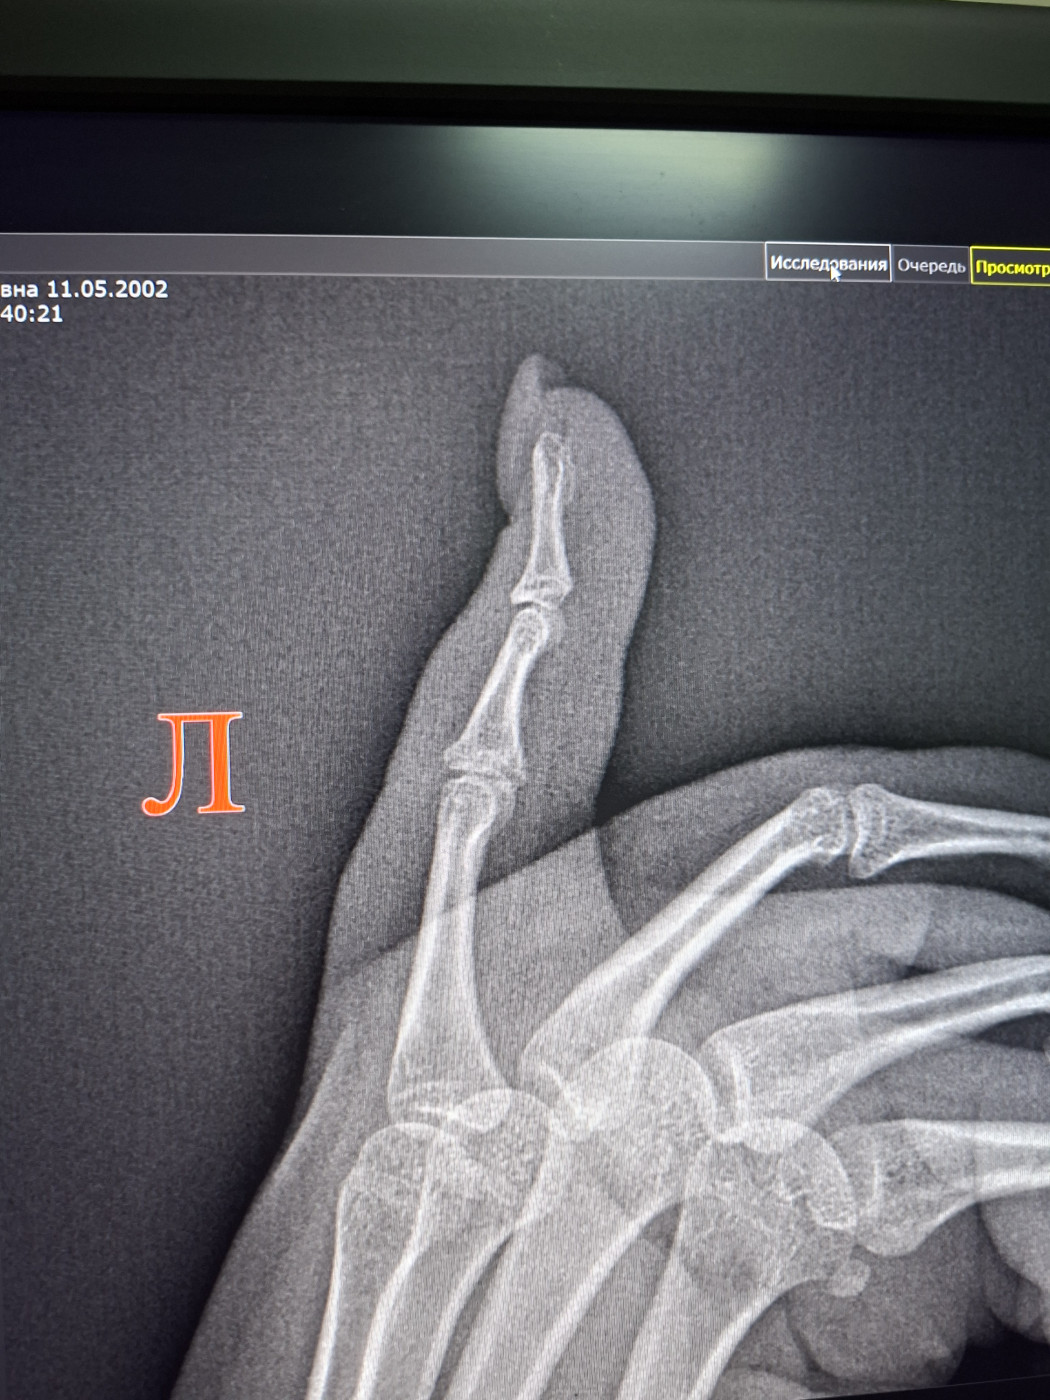

После падения, в гололед, перелом среднего пальца, на левой руке. Гипс …